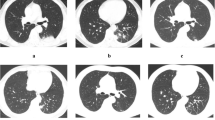

Chest CT was performed in all these patients. The imaging manifestations were diverse, as shown in Fig. 1. Table 3 shows the details of chest CT findings in immunocompromised and immunocompetent patients. The most common manifestations were pulmonary nodules (93/136, 68.4%) and patchy shadows (56/136, 41.2%). Multiple pulmonary nodules, ground-glass attenuation/interstitial changes and cavitation were more common in immunocompromised patients (P <0.05). The involvement rate of bilateral lungs was 57.4% (78/136), which mostly involving left lower lung. Lesions were more likely to involve bilateral lungs in immunocompromised patients (P <0.05). A total of 47 patients were misdiagnosed as tuberculosis or tumor. Immunocompromised PC patients were more likely to be misdiagnosed as tuberculosis than immunocompetent patients, and tumor was more likely to be considered in immunocompetent patients, but there was no significant difference (P >0.05).

The findings of chest computed tomography of pulmonary crypotoccosis (immunocompetent patients: (a–e); immunocompromised patients: (f–h): (a) ground glass attenuation; (b) a single small nodule; (c) multiple lung nodules; (d) patchy shadows with air bronchogram; (e) nodular shadow with spiculate boundary; (f) pulmonary cavity; (g) scattered irregular patchy consolidation, nodules and mass shadows in bilateral lungs, and formation of cavities in a few lesions; (h) shadows of miliary nodules in bilateral lungs.